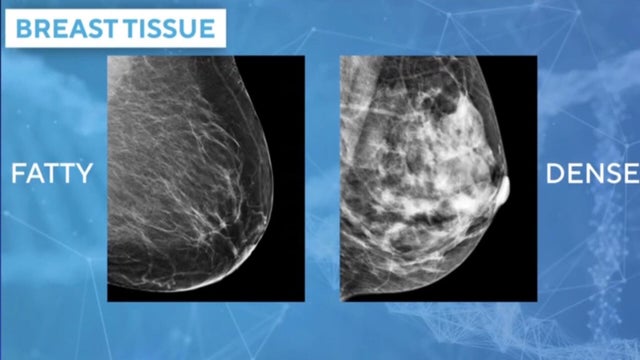

Breast cancer is the second-leading cause of cancer deaths in women. About one in eight women will be diagnosed with the disease in their lifetimes. To combat that, some doctors are using AI as a tool to help them not only detect breast cancer, but also predict a woman's risk factors. Dr. Connie Lehman, founder of Clarity, joins CBS News to discuss the first FDA-authorized AI platform used to predict a woman's 5-year risk of developing breast cancer.